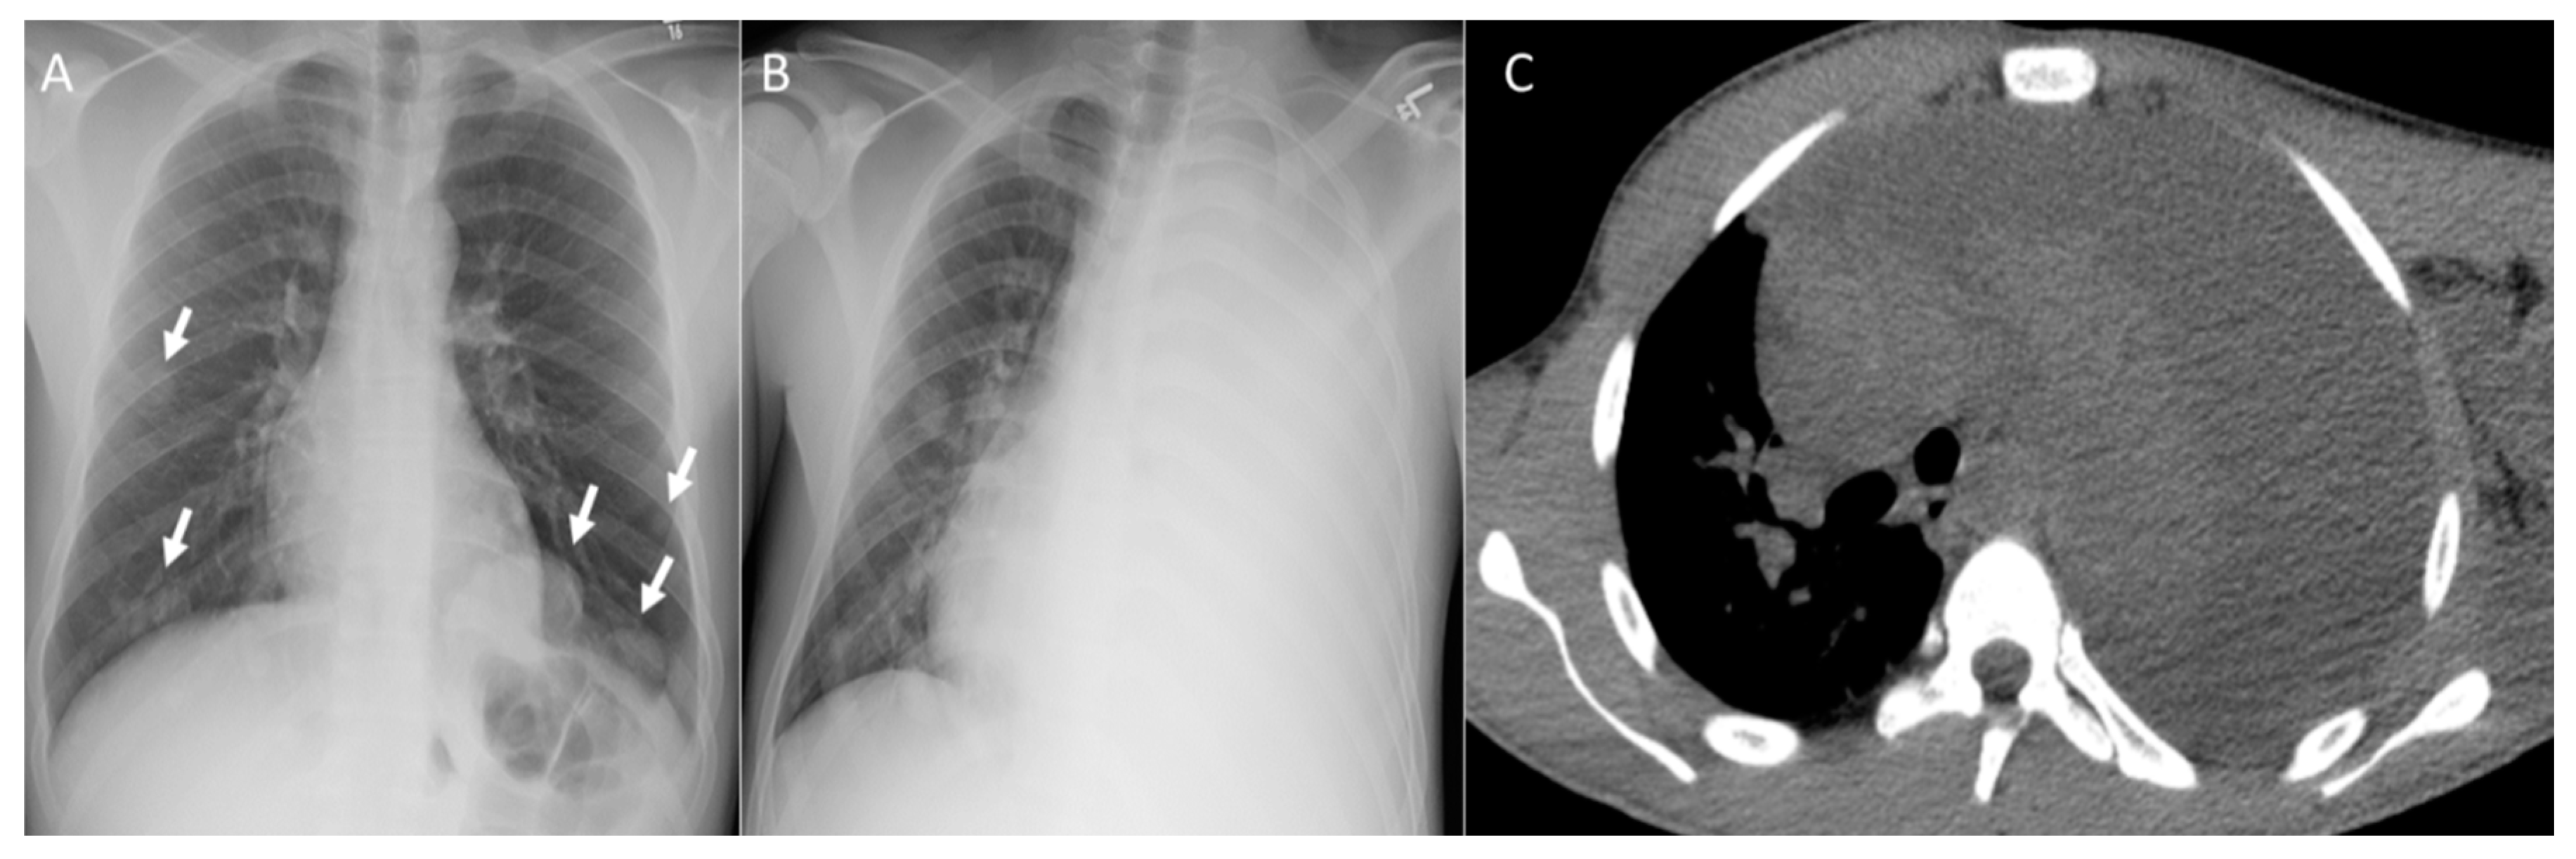

3. Pleura

6. Chest Wall

7. Role of Chest CT